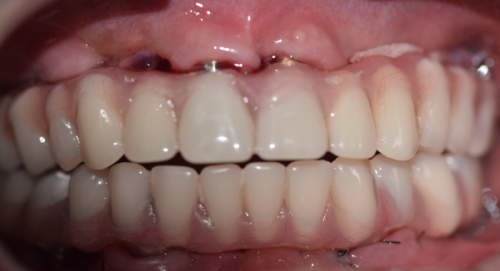

虽然种植牙不能用医疗保险报销,但了解其费用构成和影响因素,能让患者更好地规划自己的支出。种植牙的费用主要包括种植体的费用、基台的费用、牙冠的费用以及手术费用和检查费用等。种植体的品牌和材质是影响费用的重要因素,不同的品牌和材质价格差异较大。例如,进口的高端种植体价格可能会比国产的种植体高出特别多。牙冠的材料也有多种选择,如烤瓷牙冠、全瓷牙冠等,全瓷牙冠相对来说价格会更贵一些。此外,患者的口腔状况也会影响费用,如果患者口腔存在炎症、骨量不足等问题,可能需要精良行相应的治疗,这也会增加整体的费用。

总结来说,就目前的情况而言,“种植牙可以用医疗保险吗”这个问题的答案大多是否定的。种植牙一般不在医疗保险报销范围内,主要因为其属于牙齿修复的美容范畴。但患者也不用过于担心费用问题,可以通过对比医院价格、关注优惠活动、选择合适的付款方式等策略来减轻经济压力。同时,也可以期待未来医疗保险政策的变化,说不定会给种植牙患者带来更多的实惠。如果您有种植牙的需求,不妨多了解相关信息,再根据自己的实际情况做出决策。